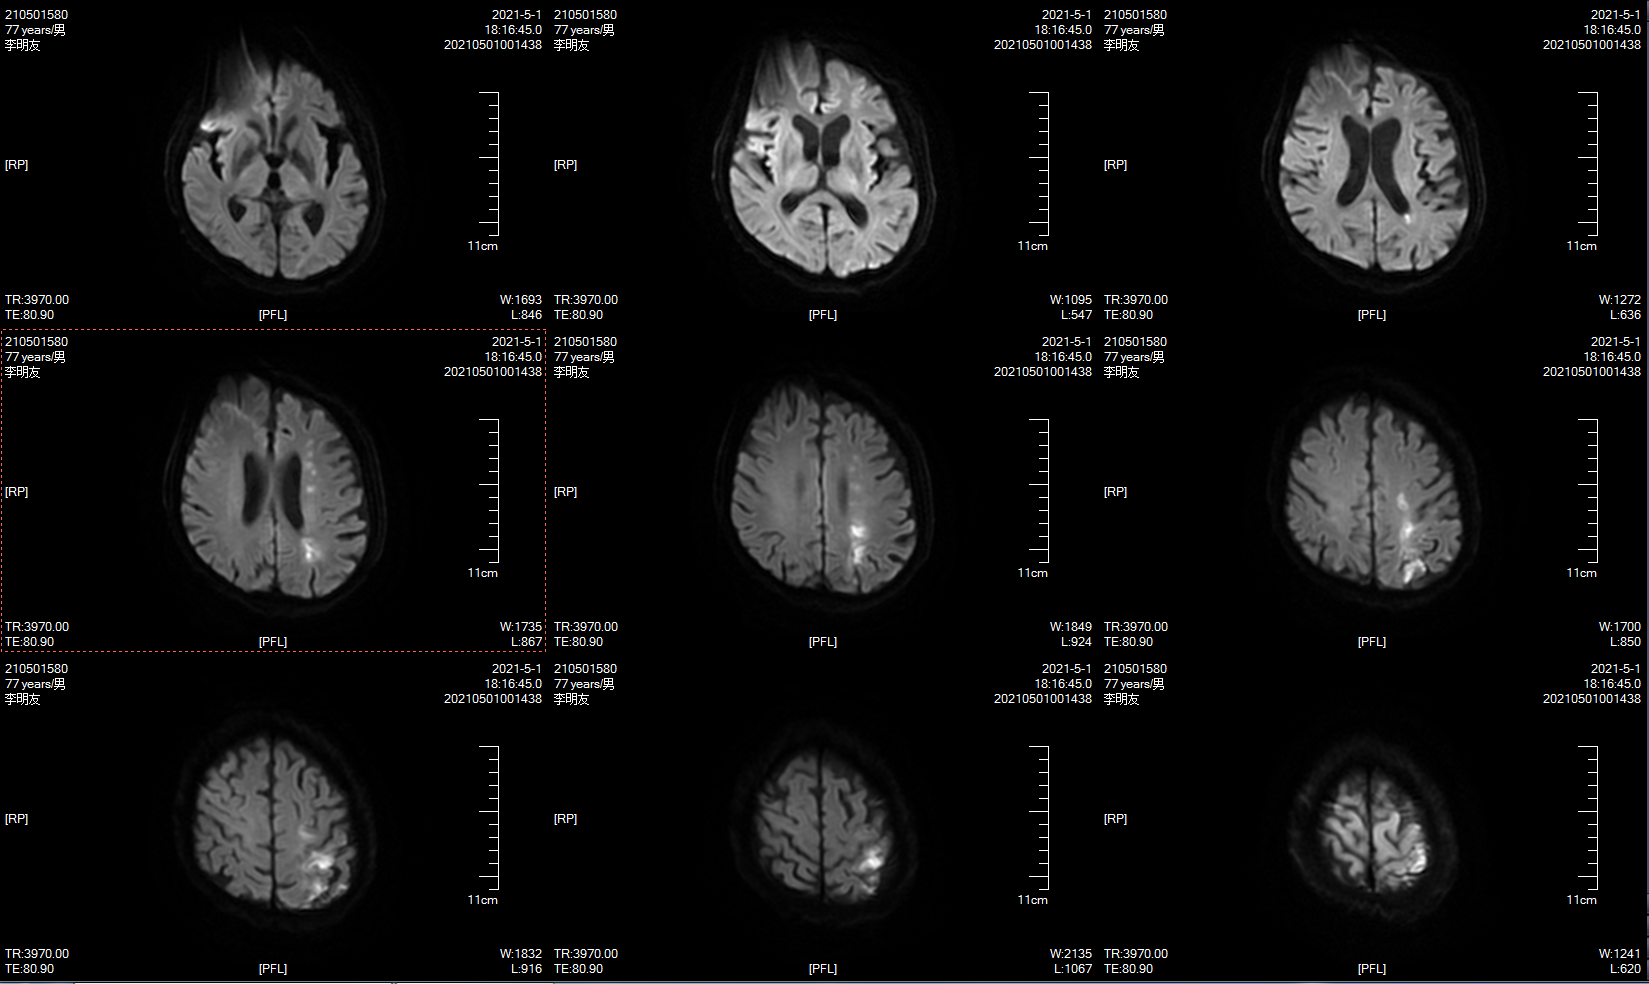

本次MRI示左侧分水岭多发梗死